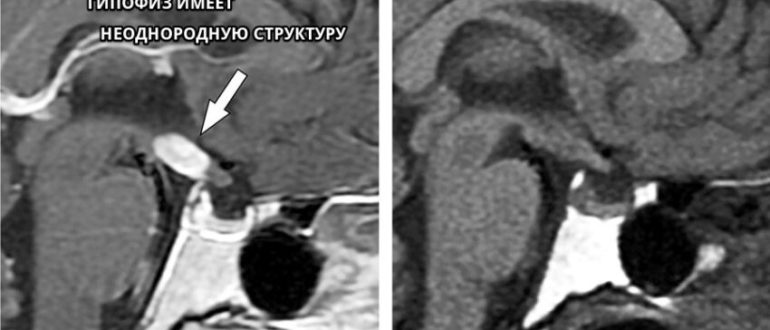

МР картина диффузно неоднородной структуры аденогипофиза

Что такое диффузно-неоднородная структура гипофиза и чем это опасно Гипофиз или питуитарная железа, играет важную роль в работе организма, продуцируя большинство жизненно важных гормонов. В нормальном состоянии, нижняя…